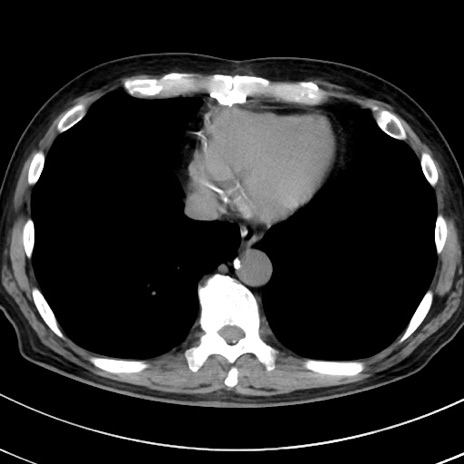

症例38(横断像)

【症例】70歳代 男性

【主訴】腹痛・嘔吐

【現病歴】昨晩より、嘔吐・腹痛あり。今朝になっても嘔吐あり。来院。

【既往歴】心臓バイパス手術、開腹胆摘、腸閉塞

【身体所見】BP 107/71mmHg、HR 116/min、腹部:平坦、軟、下腹部に軽度圧痛あり。反跳痛なし。

【データ】WBC 15100、CRP 0.32